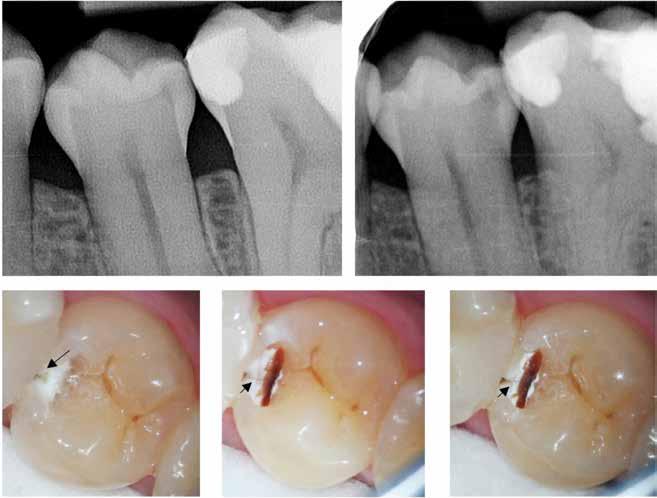

Fig. 2. Med udgangspunkt i tænder med stigende sammenbrud af en dentineksponeret carieslæsion kan et forventeligt billede af et fremadskridende mønster af ubehandlet caries fremstilles. Jo flere sammenbrudte dentinflader, desto mere åbenlæsions-topologi (A-E). I forhold til radiologisk penetrationsdybde tæt på pulpa vil dybdelæsioner med synlig radioopak zone mellem læsion og pulpa have lav risiko for bakterier i pulpa (F) overfor ekstremt dybe læsioner, der har radiologisk kontakt til pulpa (G). Læsionens topologi har konsekvenser for vækstbetingelserne af en biofilm. ”Lukkede” dentin-caries-læsioner har tydelig biofilmakkumulering, blød gullig/lysbrun dentinoverflade og med et underminerende spredningsmønster langs med emalje-dentin-grænsen (H). I modsætning til ”åbne” læsioner, der er mere mørkfarvede uden nævneværdig akkumulering af biofilm (I). (Med tilladelse fra (16) og Wiley).

Fig. 2. A picture of a progressing pattern of one untreated caries lesion is expected based on teeth with increasing break-down of a dentine-exposed carious lesion, and this is confirmed in this figure. The more surfaces that are involved in a cavity the more “open” topology (A-E). In relation to the radiological penetration depth close to the pulp, deep lesions with a visible radiopaque zone between the lesion and the pulp will have a low risk of bacteria in the pulp (F) compared to extremely deep lesions that have radiological contact with the pulp (G). The topology of the lesion has consequences for the growth conditions of a biofilm. "Closed" dentin caries lesions have clear signs of biofilm accumulation, a soft yellowish/light brown dentin surface and with an undermining spreading pattern along the enamel-dentine border (H). In contrast to “open” lesions that are darker in colour without appreciable accumulation of biofilm (I). (With permission from (16) and Wiley).

& klinik ∕ oversigtsartikel

B A F G H I C

470 T ∕

D E

filmen, og deres produktion af organiske syrer fører til demineralisering af de hårde tandvæv (emalje, dentin og cement). I begyndelsen vil demineraliseringen ikke føre til en egentlig kavitetsdannelse på tandoverfladen til trods for, at der både er mineraltab i emalje og dentin, men den gradvise demineralisering over tid vil ubehandlet kunne svække emaljelæsionens centrale dele. De mastikatoriske kræfter vil føre til dannelse af mikrokaviteter efterfulgt af egentlige kliniske kaviteter (Fig. 1). På sigt fører dette til, at den demineraliserede emaljelæsion bryder sammen og eksponerer den underliggende demineraliserede dentin. På dette tidspunkt siges læsionen at være kaviteret eller klinisk dentin-eksponeret. Hvorvidt en carieslæsion progredierer eller ej, beskrives konceptuelt med begrebet “cariesaktivitet” eller “læsionsaktivitet”. Begrebet dækker både over, hvorvidt der ses akkumulering af biofilm på overfladen af carieslæsionen, samt hvorvidt man klinisk kan se tegn på aktiv produktion af syre i den akkumulerede biofilm. Cariesaktivitet kan tillige bekræftes radiologisk (Fig. 1A og B). En aktiv carieslæsion er kort sagt dækket af en cariogen biofilm og vil derfor progrediere med øget penetrationsdybde af læsionen til følge, hvorimod en inaktiv carieslæsion ikke på samme måde har en overfladebiofilm og heller ikke vil udvikle sig med særlig stor hastighed (1). Om end inaktive carieslæsioner vil kunne aktiveres på ny, er den nuværende kliniske forståelse, at intervention ikke umiddelbart er nødvendigt eller i det mindste kan begrænses kraftigt i tilfælde af inaktive læsioner. Muligheden for akkumulering af biofilm, selv i en kaviteret carieslæsion, afhænger til en vis grad af, hvorvidt carieslæsionen kan beskrives som værende “lukket” eller “åben” (16). Jo færre tandflader der er involveret i en kaviteret carieslæsion, jo mere “lukket” eller “skålformet” vil læsionens topologi være (Fig. 2A-E), hvilket tillader akkumulering af biofilm i læsionsmiljøet. En carieslæsion med et lukket læsionsmiljø vil derfor som oftest være en aktiv læsion, hvorimod åbne carieslæsioner ikke vil kunne akkumulere biofilm i samme omfang og derfor vil forventes at have en tilsvarende lavere progressionshastighed til trods for et ellers fremskredent stadie. Aktive dentin-caries-læsioner dækket af biofilm vil klinisk kunne beskrives som værende hvidlige/gullige/lysbrune (Fig. 2H-I), og den carierede dentin vil være blød og ikke mindst fugtig eller våd. I modsætning hertil fremstår inaktive læsioner mørkfarvede, læderagtige og uden nævneværdig akkumulation af biofilm (Fig. 2I). Desuden udviser inaktive carieslæsioner ikke samme grad af fugtighed (22). Progression og spredning af en aktiv carieslæsion vil ikke blot føre til øget penetrationsdybde, men også lede til underminering af emaljen. Dette kan ses som retrograd demineralisering (Fig. 2H). I takt med at carieslæsionen gradvist underminerer emaljen, vil emaljen på et tidspunkt være så u-understøttet, at den almindelige tyggefunktion vil føre til, at emaljen knækker af. Et resultat af dette er, at carieslæsionen bliver mere “åben”. I den nu relativt mere åbne carieslæsion vil akkumulering af biofilm ikke kunne finde sted i samme omfang som før (Fig. 2I), og carieslæsionens progressionshastighed eller aktivitet vil mindskes eller stoppe fuldstændigt (16,23). Dette dynamiske skift imellem aktivitet og inaktivitet kan ses ved både dybe og mindre dybe carieslæsioner og danner fra et klinisk perspektiv